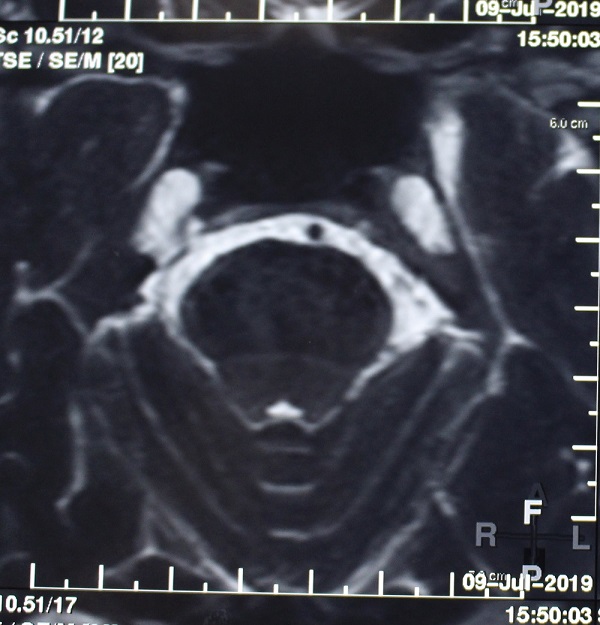

Hình chụp MRI cho thấy mạch máu bị chèn ép lên dây thần kinh tam thoa.

Ngày 18/10/2019, chị H.L nhập viện Bệnh viện Quốc tế City. Sau khi khai thác bệnh sử và thực hiện thăm khám kỹ càng, chụp MRI bác sĩ chẩn đoán bệnh nhân bị đau dây thần kinh tam thoa, rối loạn giấc ngủ. Sau khi hội chẩn, 9h00 ngày 19/10/2019, các bác sĩ Ngoại Thần Kinh Bệnh viện Quốc tế City đã phẫu thuật cho bệnh nhân bằng phương pháp “Phẫu thuật giải ép vi mạch”.

BS.CKII Lê Trọng Nghĩa, Khoa Ngoại Thần Kinh Bệnh viện Quốc tế City, bác sĩ trực tiếp mổ cho bệnh nhân H.L đã chia sẻ, đau dây thần kinh tam thoa (hay dây thần kinh V) nguyên phát có các tính chất rất đặc trưng là đau đột ngột, cơn ngắn vài giây đến vài chục giây, có chu kỳ. Tính chất đau như cắt, đau chói, hay như điện giật. Ngoài cơn đau bệnh nhân như bình thường. Đau có thể xảy ra bất kỳ vùng chi phối cảm giác nào của dây thần kinh số V trên khuôn mặt. Tuy nhiên, vùng hay bị nhất là nhánh hàm trên và nhánh hàm dưới với biểu hiện đau buốt răng hàm. Cơn đau có thể khởi phát sau các hoạt động như nhai, nuốt, rửa mặt, đánh răng, gió thổi vào mặt hoặc có kích thích không đặc hiệu ở vùng mặt. Cho đến nay nguyên nhân của bệnh lý này được chứng minh là do dây thần kinh số V bị chèn ép bởi một hay nhiều nhánh mạch máu bên trong não.